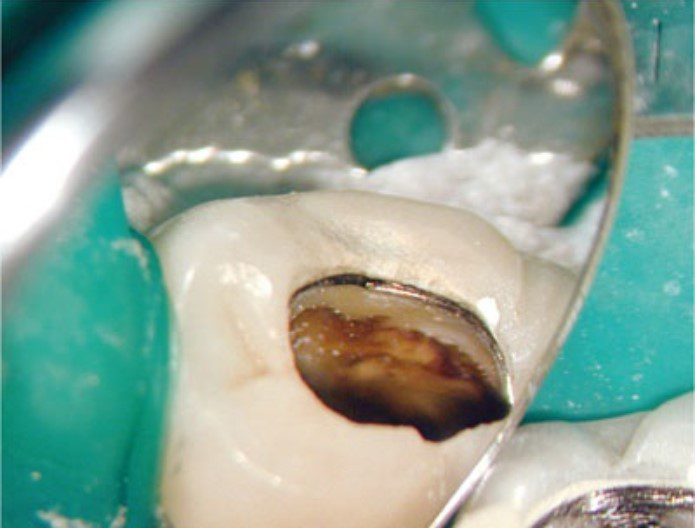

Thông thường, răng cần điều trị nội nha thường đã được phục hồi lớn trước đó hoặc bị bể vỡ và nhiễm khuẩn.

Cần loại bỏ mô sâu răng để ngăn ngừa rò rỉ và giảm nguy cơ mảnh ngà sâu chứa vi khuẩn đi vào ống tủy trong quá trình điều trị.

Mở tủy

Nếu xoang mở tủy không đạt yêu cầu thì việc xác định và thăm dò ống tủy sẽ trở nên phức tạp hơn, tiên lượng điều trị sẽ bị ảnh hưởng do bị hạn chế làm sạch, khử khuẩn và trám bít.

Ngoài ra, còn có thể làm tăng nguy cơ gãy dụng cụ và tạo hình sai (ví dụ như lệch đường, tạo khấc), dẫn đến kiểm soát nhiễm khuẩn kém và cuối cùng là thất bại điều trị.

Thực tế thì hiếm khi xoang mở tủy có hình dạng hoàn toàn giống mô tả điển hình trong sách giáo khoa — tức là hình dạng của răng trẻ, chưa từng được phục hồi.

Trên thực tế thì kích thước buồng tủy và vị trí miệng ống tủy bị ảnh hưởng bởi lượng và vị trí ngà thứ cấp, ngà bậc ba được bồi đắp để đáp ứng với sâu răng, phục hồi, rò rỉ hoặc mòn răng theo thời gian.

Những tác động tích lũy này có thể làm thay đổi đáng kể kích thước và hình dạng buồng tủy.